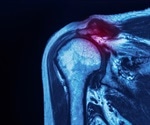

What are Rotator Cuff Injuries?

What is the Rotator Cuff?